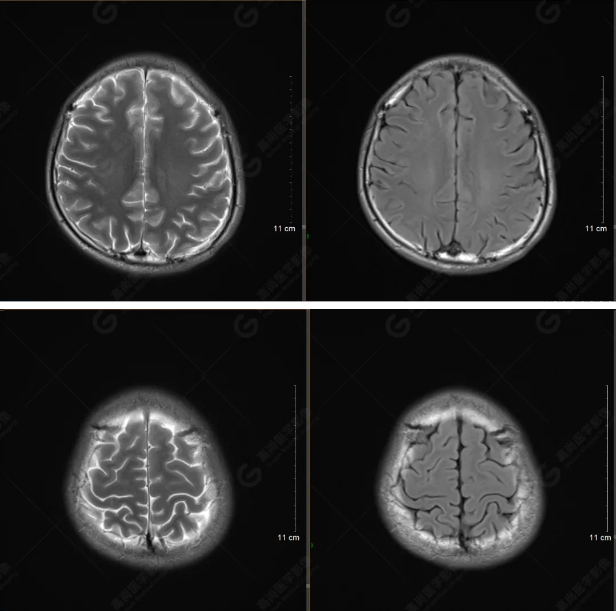

以下是T1WI軸位掃描及矢狀位掃描:

雙側(cè)大腦半球?qū)ΨQ,灰白質(zhì)對比正常,顱內(nèi)未見異常信號影。腦室系統(tǒng)未見擴(kuò)大,中線結(jié)構(gòu)居中。腦溝、裂未見增寬。幕下小腦、腦干未見異常。矢狀位示垂體形態(tài)、大小級信號未見異常。所示左側(cè)乳突內(nèi)見多發(fā)短T1長T2信號影。

顱腦MRI平掃未見明顯異常,左側(cè)乳突內(nèi)積血,建議補(bǔ)充SWI檢查。(左側(cè)為薄層原始圖像,右側(cè)為后處理5mm圖像)